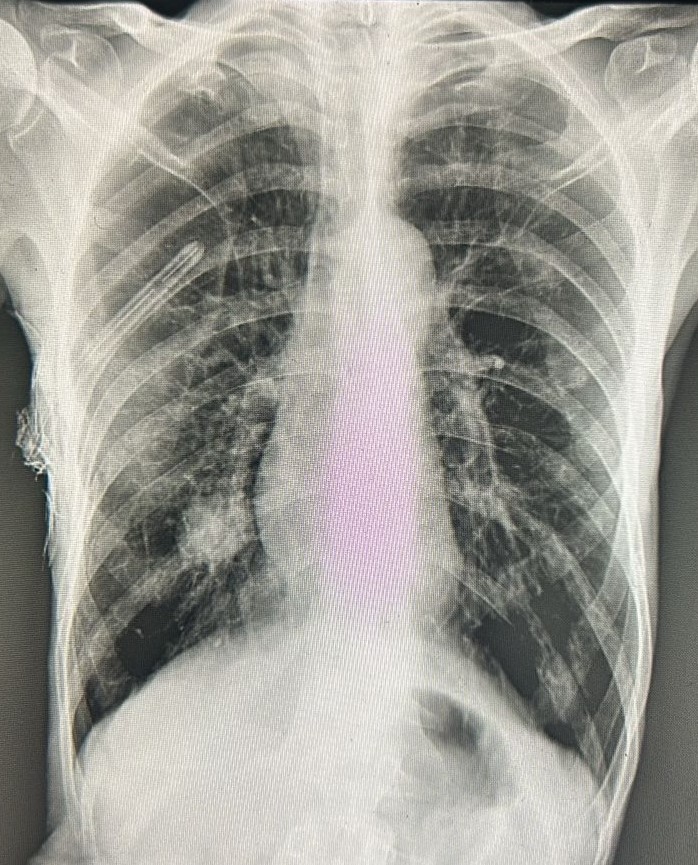

| 5 | IGGMC, Nagpur, Nagpur | P2 | 29-4467 | Meera Gohare | Consent taken on Paper | 64 Yrs. |

Provisional Diag : ?

Final Diag : Disseminated TB (Miliary TB With Abdomen Koch) |

TB Case (Confirmed) | Abnormality visible on x-ray |

View |

||||